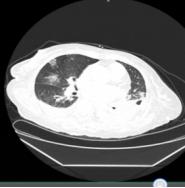

患者2020年2月10日因“咳嗽气促2天”于外院住院治疗,时咳嗽少痰,气促,活动后加重,伴双下肢水肿,夜可平卧,无发热,无胸闷痛,无呕吐,无腹痛腹泻。查胸部CT提示“双肺磨玻璃样改变”,新型冠状病毒核酸检测阳性。西医诊断为新型冠状病毒肺炎。予抗感染、抗病毒治疗后(具体治疗经过不详),患者气促、咳嗽症状缓解,为求进一步诊治于2月20日入住雷神山医院。入院后,西医常规给予酒石酸美托洛尔片(倍他乐克)控制血压、人血白蛋白提高白蛋白配合呋塞米利尿等治疗。

入院血常规提示白细胞计数及中性粒细胞绝对值升高,淋巴细胞绝对值偏低。胸部CT提示双肺感染,考虑病毒性肺炎可能,双侧胸腔积液,双肺下叶膨胀不全(图2-4-55)。

图2-4-55 2020年2月20日胸部CT